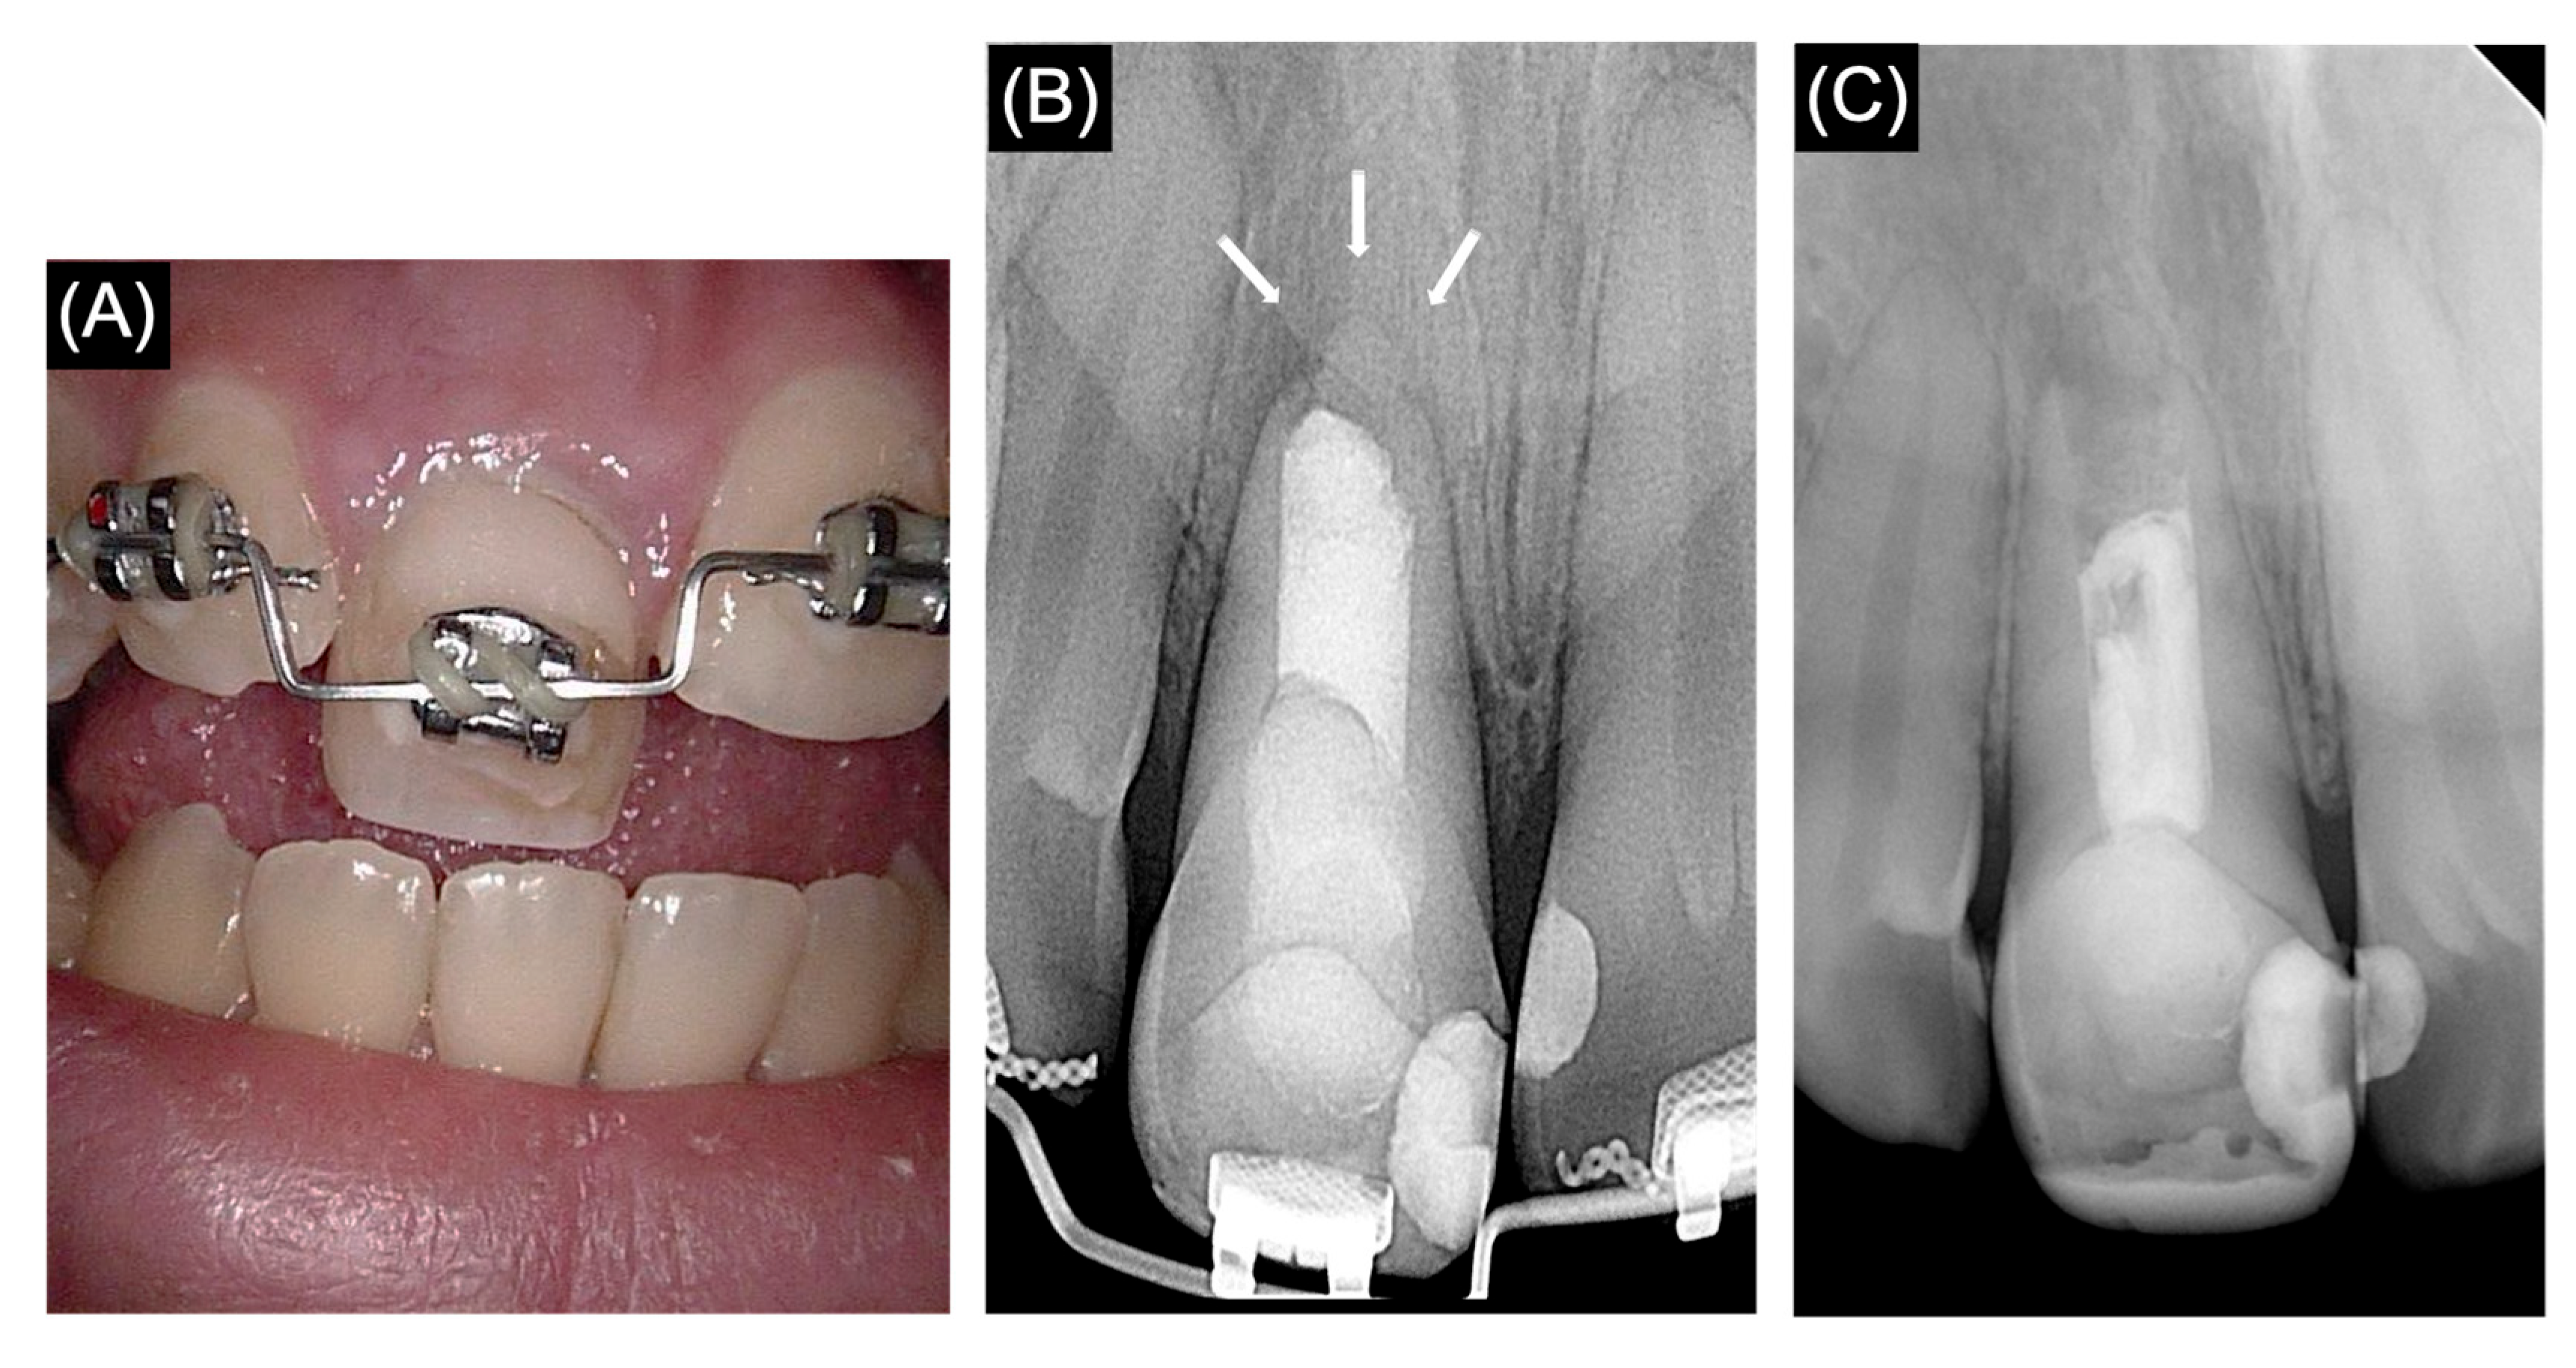

2.2. Second Treatment Visit

2.3. Follow-Up Visit